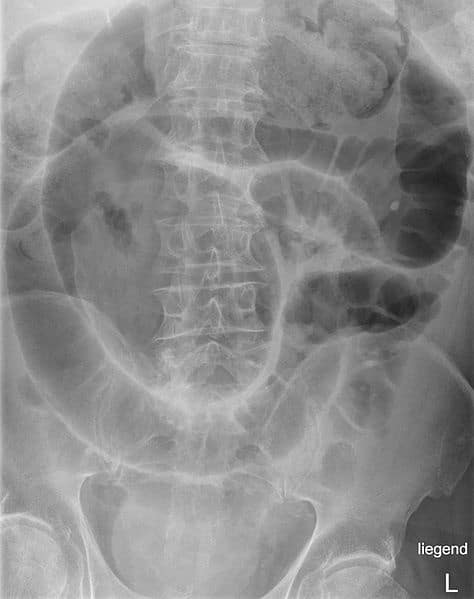

The mesentery is a double fold of peritoneal tissue that suspends the small intestine and large intestine from the posterior abdominal wall. It was previously thought to be a collection of discrete structures – each with separate insertions into the posterior wall. However, recent research has found the mesentery to be one contiguous structure, which has led to proposals for its reclassification as an organ. In this article, we shall look at the anatomy of the mesentery – its anatomical structure, vasculature, innervation, lymphatics and clinical relevance. Note: Research regarding the mesentery is relatively recent, and some older textbooks may still describe the different parts of the mesentery as separate structures – this is now thought to be incorrect. By TeachMeSeries Ltd (2025) Fig 1Simplified illustration of the mesentery. It acts to connect the small intestine and large intestine to the posterior abdominal wall. Pro Feature - 3D Model You've Discovered a Pro Feature Access our 3D Model Library Explore, cut, dissect, annotate and manipulate our 3D models to visualise anatomy in a dynamic, interactive way. Learn More Function The mesentery has several functions in the abdomen: Suspends the small and large intestine from the posterior abdominal wall; anchoring them in place, whilst still allowing some movement. Provides a conduit for blood vessels, nerves and lymphatic vessels. Postulated to play a pathological role in inflammatory diseases such as Crohn’s disease. Pro Feature - Dissection Images Prosection of the abdomen with the greater omentum reflected back to reveal the small intestine. Prosection of the abdomen with the greater omentum reflected back to reveal the small intestine. You've Discovered a Pro Feature Access our Dissection Image Library Enhance your understanding with high-resolution dissection images showcasing real-life anatomy. Learn More Structure The mesentery is formed by a double layered fold of peritoneum. Although the mesentery is now thought to be a contiguous structure, subsections of the mesentery can be named according to the viscera it is associated with. Thus, names such as mesocolon, mesorectum, mesosigmoid all relate to different parts of the mesentery. The ‘root’ of the mesentery is the point where the mesentery attaches to the posterior abdominal wall, and is therefore a ‘bare area’. Due to the range of abdominal organs the mesentery envelopes, the root is long, narrow and has an oblique orientation, from the left side of the L2 vertebra to the right sacroiliac junction roughly. In the gastrointestinal tract, there are six flexures of note: duodenojejunal, ileocaecal, hepatic, splenic, and those between the descending and sigmoid colon and the sigmoid and rectum. These flexures are often used to mark the distinction between different portions of the mesentery: Mesentery of the small intestine – connects the loops of jejunum and ileum to the posterior abdominal wall and is a mobile structure. (1) Right mesocolon – flattened against the posterior abdominal wall (2) Transverse mesocolon – a mobile structure and lies between the colic flexures (3) Left mesocolon – flattened against the posterior abdominal wall (4) Mesosigmoid – has a medial portion which is flattened against the posterior abdominal wall, whereas the region of mesentery associated with the sigmoid colon itself is mobile. (5) Mesorectum – assists in anchoring the rectum through the pelvis.(6) By TeachMeSeries Ltd (2025) Fig 2Small intestine and and large intestine highlighted to show associated mesentery. The areas of the mesentery that are flattened against the posterior abdominal wall (the right and left mesocolon and the medial mesosigmoid) are attached to the abdominal wall via an additional layer of connective tissue known as Toldt’s fascia. The fascia contains several lymphatic channels. Clinical Relevance Intestinal Volvulus A volvulus occurs when a loop of intestine twists around itself and its mesentery, causing obstruction of the bowel. It is possible that the bowel will twist tightly enough to prevent the blood supply to the intestine, and result in bowel infarction. The most commonly affected area of bowel is the sigmoid colon. The risk of intestinal volvulus is increased in children with intestinal malrotation, a congenital defect in which the embryological intestinal rotation is incomplete, resulting in improper anchoring of the intestines to the posterior abdominal wall. Medical imaging (abdominal x-ray, CT abdo-pelvis) is frequently used to confirm a diagnosis, and serious cases require surgical intervention. By Hellerhoff (Own work) [CC BY-SA 3.0], via Wikimedia Commons Fig 3Abdominal x-ray demonstrating a sigmoid volvulus Vasculature The mesentery acts a conduit for neurovascular structures. The superior and inferior mesenteric arteries (SMA and IMA) arise from the abdominal aorta and travel in the mesentery to supply the abdominal viscera. These vessels also give rise to branches that supply the mesentery itself. Superior mesenteric artery – supplies the organs of the midgut – from the major duodenal papilla to the proximal two thirds of the transverse colon. Inferior mesenteric artery – supplies the organs of the hindgut – the distal one third of the transverse colon, splenic flexure, descending colon, sigmoid colon and rectum. The venous drainage of the mesentery is via the superior mesenteric vein (SMV) and inferior mesenteric vein (IMV), which both run alongside their associated arteries. By TeachMeSeries Ltd (2025) Fig 4The superior mesenteric artery and its branches. Note: the inferior pancreatoduodenal artery arises more proximally, and is not visible on this illustration. By TeachMeSeries Ltd (2025) Fig 5Major branches of the inferior mesenteric artery demonstrated in green Innervation The superior mesenteric plexus (a continuation of the celiac plexus) accompanies the superior mesenteric artery into the mesentery. The superior mesenteric plexus then divides into many secondary plexuses which contain parasympathetic and sympathetic innervation to the mesentery associated with a particular organ, the organs themselves and their related blood vessels. Lymphatics The mesentery contains both lymph nodes and lymphatic vessels. There are several groups of lymph nodes found within the mesentery: Inferior mesenteric lymph nodes – receives lymph from the hindgut organs, and drains into the superior mesenteric lymph nodes. Superior mesenteric lymph nodes – receives lymph from the midgut organs (and from the inferior mesenteric nodes), and drains into the pre-aortic lymph nodes. By TeachMeSeries Ltd (2025) Fig 6Lymphatic drainage of the cecum and appendix. Do you think you’re ready? Take the quiz below Pro Feature - Quiz The Mesentery Question 1 of 3 Submitting... Skip Next Rate question: You scored 0% Skipped: 0/3 1800 More Questions Available Upgrade to TeachMeAnatomy Pro Challenge yourself with over 1800 multiple-choice questions to reinforce learning Learn More Rate This Article